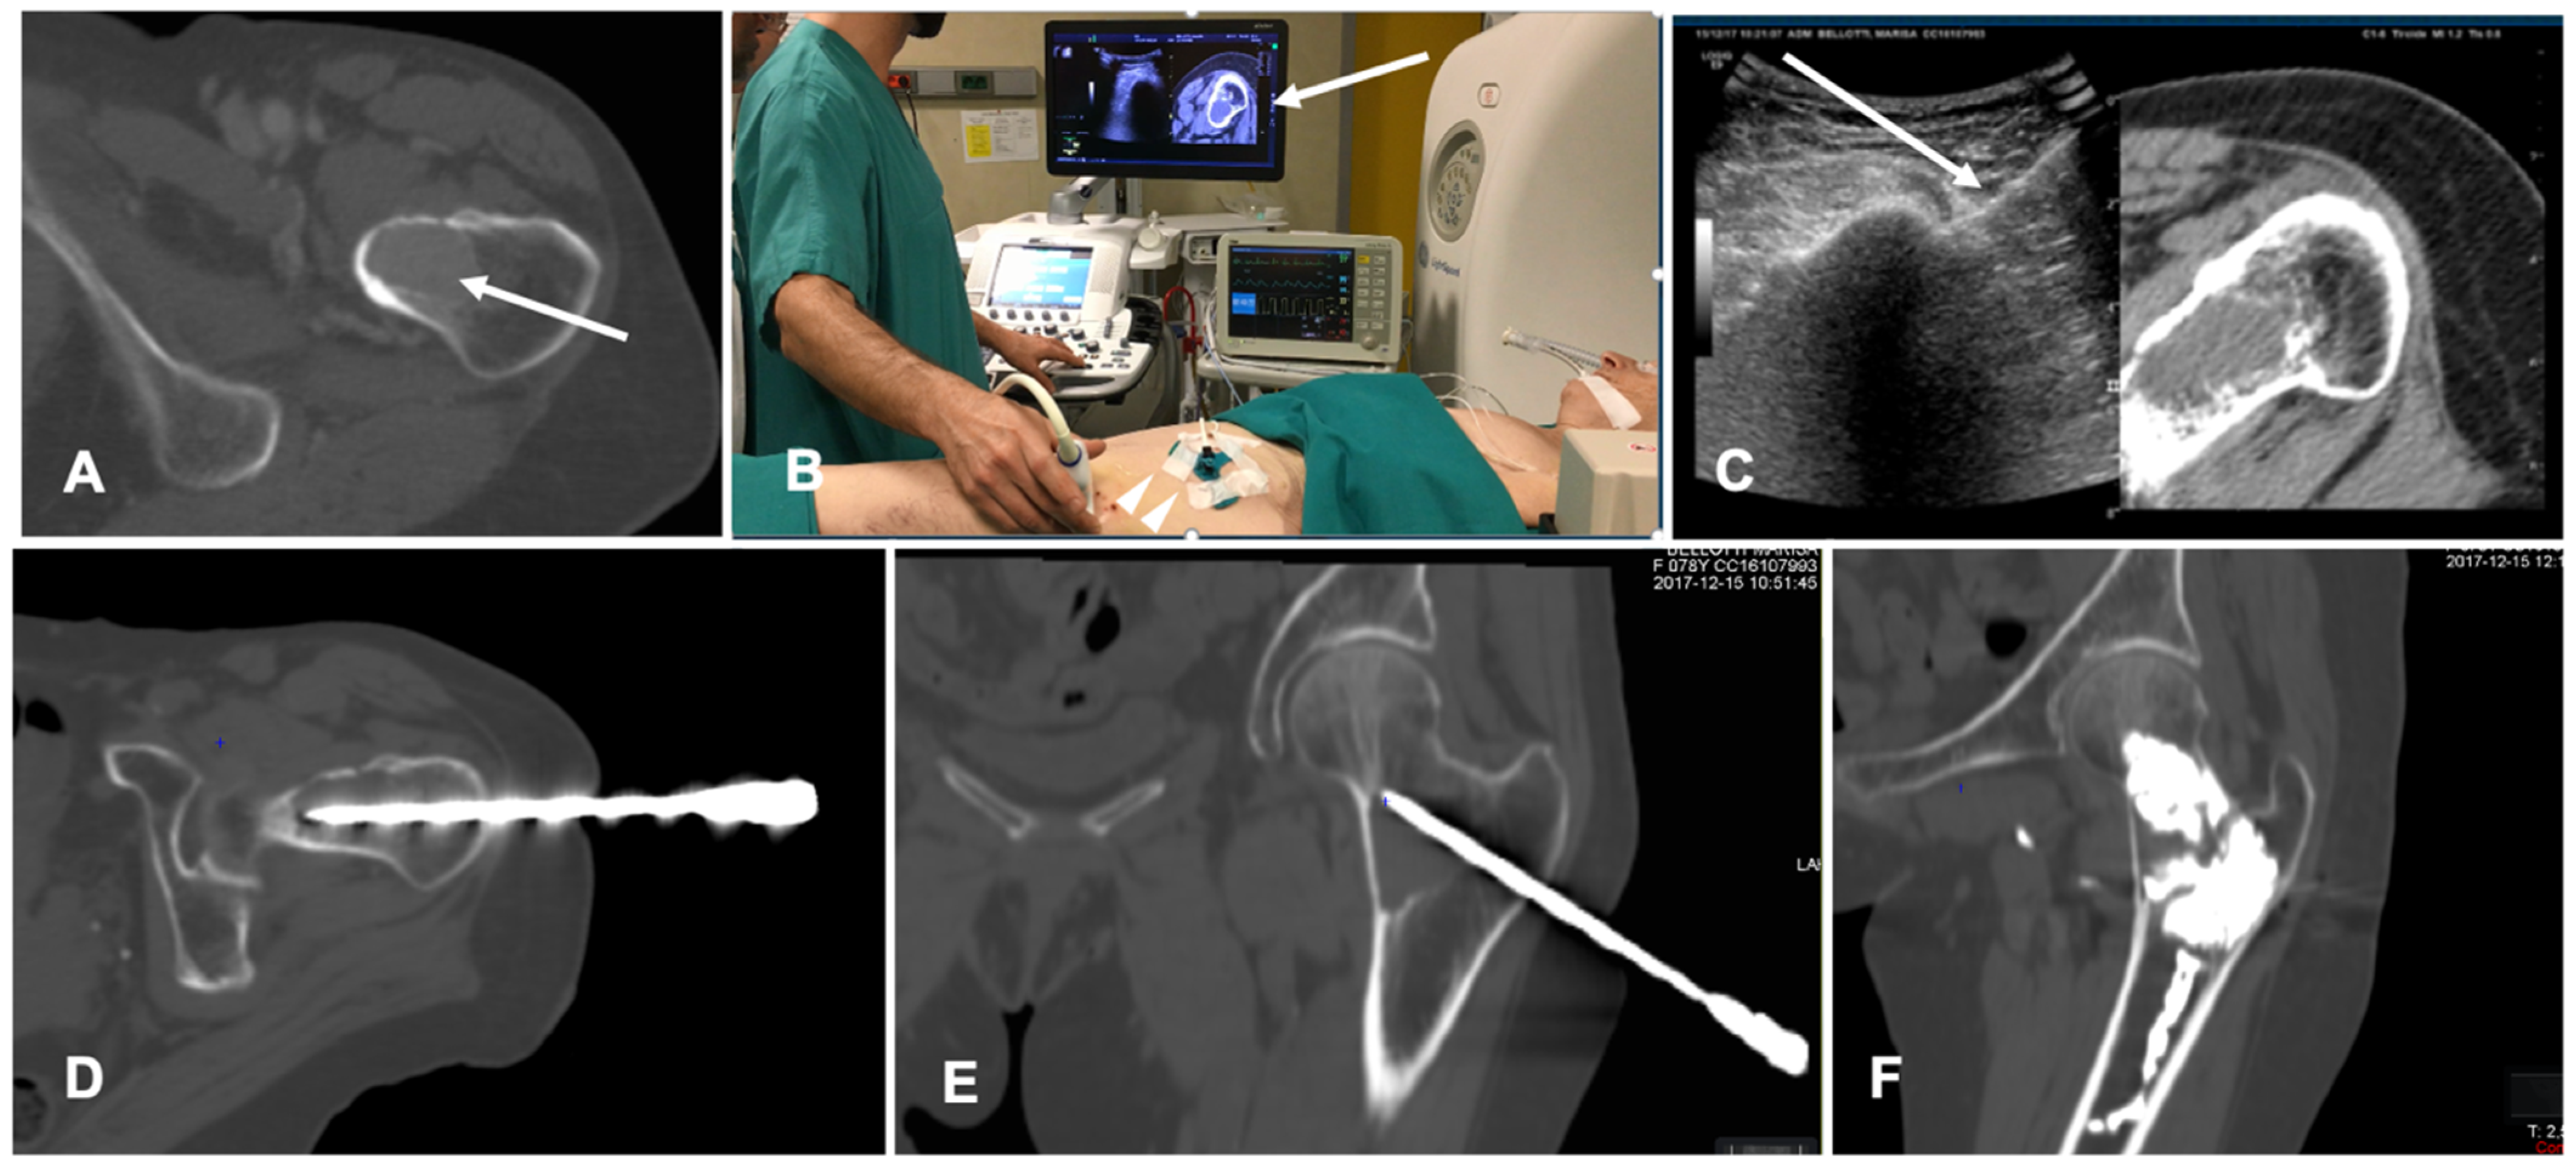

Figure 5. Case of a patient with a breast cancer femoral neck metastasis treated with cryoablation. (A) Axial view of the preoperative unenhanced Computed Tomography (CT) showing a lytic ovoid femoral neck lesion (white arrow); (B) Intraoperative setting for fusion imaging (FI): ultrasound (US) system with automatic image registration of fused images with previously acquired CT volume data sets (white arrow), a disposable locating device and sensor (white arrowheads) and electromagnetic generator (white asterisk). (C) Live FI with CT multiplanar reconstruction (right side) and US (left side). With combined CT-US imaging the needle (white arrow) can be oriented along the major axis of the bone lesion regardless the acoustic barrier. (D,E) A paraxial view and a coronal view along the needle length of the intraoperative CT confirming correct positioning into the lesion. (F) Final control CT on coronal plane after cryoablation and cementoplasty.

FI has also been tested in spine procedures. CT/US FI was demonstrated to be feasible and safe in guided bone biopsy of spinal lesions; this technique allows for continuous needle monitoring and image acquisition, avoiding the need for repeated CT scans and decreasing the number of CT passes throughout the procedure with shorter lead times compared to standard CT guidance [47]. A case of a bone ablation performed with the assistance of FI is shown in Figure 5.